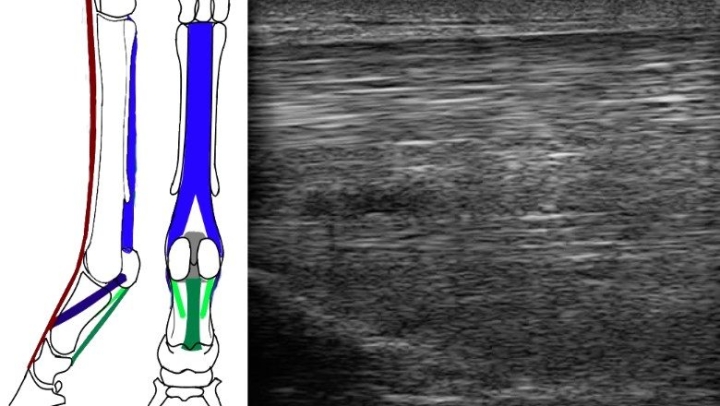

• Peesscan (echografie)

• Peesblessures bij paarden | Peesontsteking